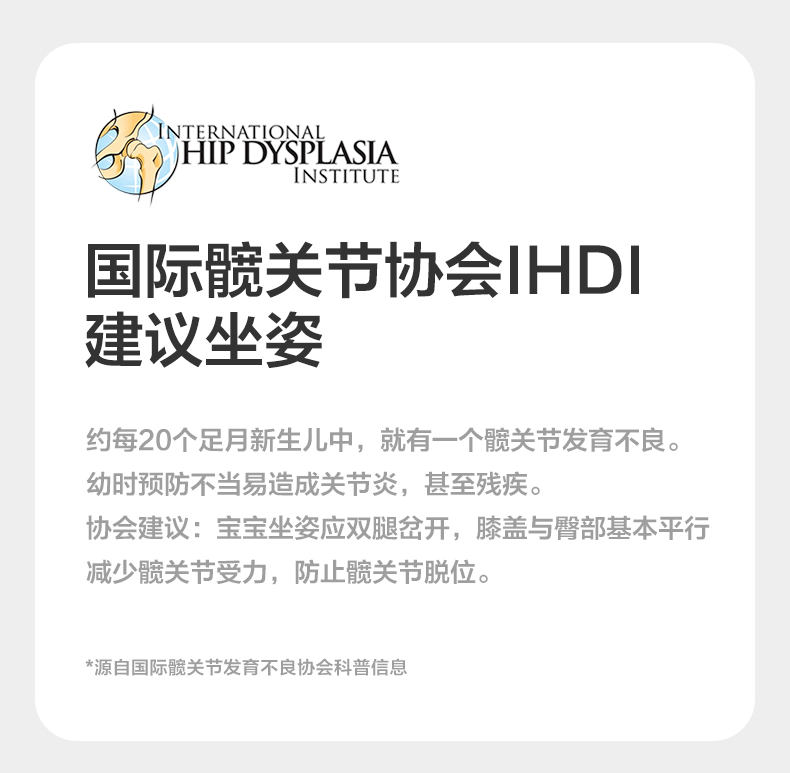

Babycare All-Level Waist Stool Baby Carrier 3-in-1 Lightweight Baby Carrier for Infants, a Handy Tool for Carrying Babies When Going Out

| Item Number | 3-in-1 Waist Stool |